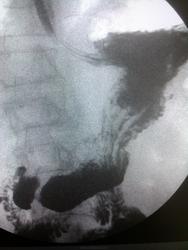

Пациент, 60 лет. На ФГДС: В антральном отделе отмечается некоторая ригидность на малой кривизне, рядом с привратником.

Не вижу изменений в антральном отделе, но обращает внимание некоторая ригидность задне-медиальной стенки субкардиально.

Обратила внимание на уплощение контура на малой кривизне препилорического отдела. Но только на одном снимке, на остальных - без особенностей. Вряд ли стоит придавать этому значение. Вы видели моторику - Вам судить

Ригидность стенки, и не только на мой взгляд, оценивается в процессе просвечивания.